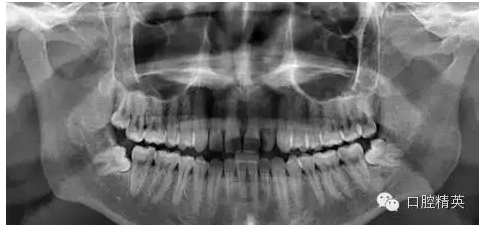

下八近中去阻微創(chuàng)拔牙

主訴 : 牙齒反復(fù)膿腫,一月前曾張口受限,要求拔出牙齒。

診斷 : 下八近中中位阻生

1、拔除前口內(nèi)全景片

7、拔牙后全景片